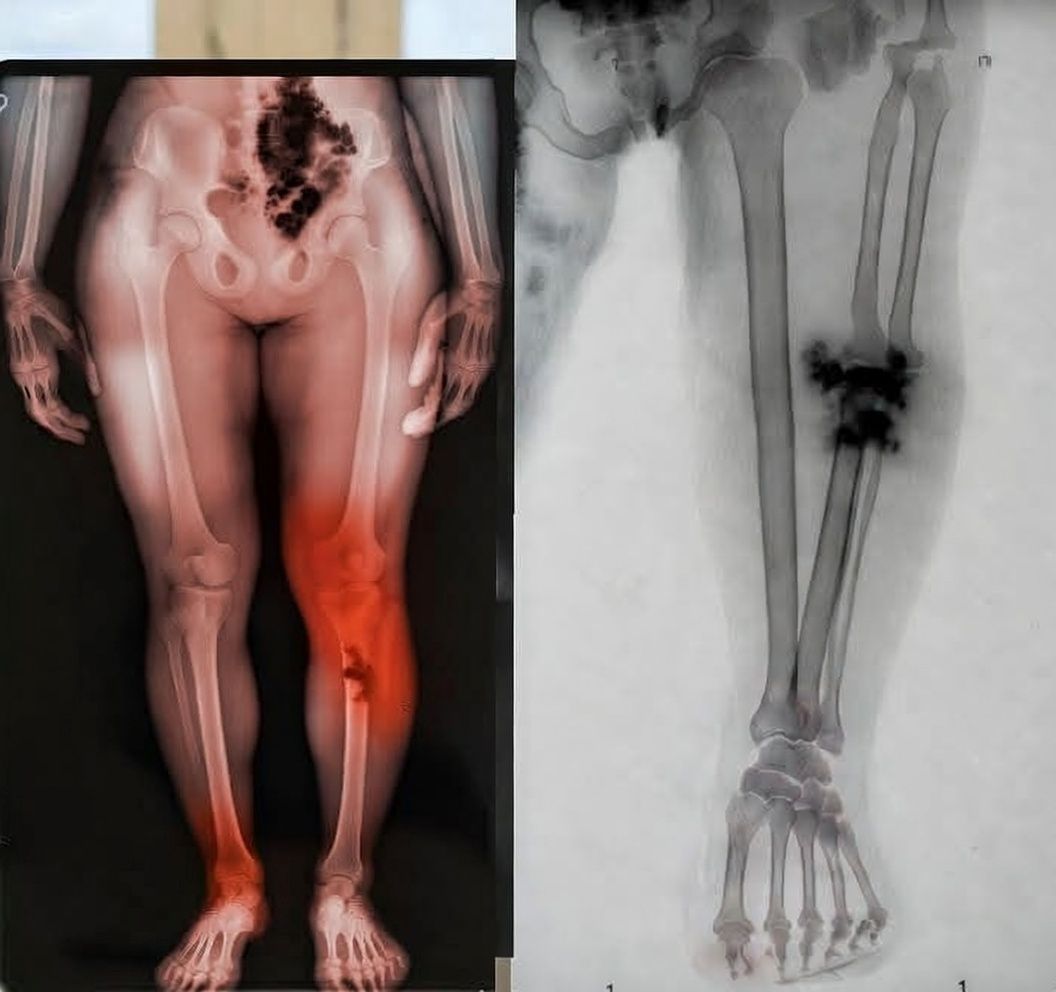

Los síntomas de este nuevo mal que acecha a los “pinchados” son terroríficos porque son silenciosos. Empieza con piquetes en el pecho, luego se te duermen las manos, sientes una neblina mental que no te deja ni sumar dos más dos, y tu sangre… ¡ay, Diosito! Dicen que la sangre se empieza a poner espesa, como chapopote.

- Moretones fantasma: Si amaneces como si te hubiera agarrado a golpes el Canelo y no recuerdas haberte pegado, tu sangre está pidiendo auxilio.